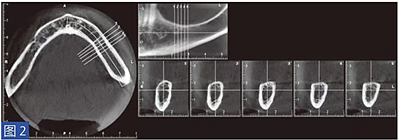

對萎縮的牙弓進行了初步的錐形計算機斷層(CBCT)掃描,以評估硬組織的三維形態(tài)。根據(jù)這些數(shù)據(jù)用特殊的環(huán)氧基熱固型光敏樹脂(3DIEMME) 打印頜骨模型。這個環(huán)氧樹脂的解剖形態(tài)模型用于作為骨重建手術(shù)術(shù)前設(shè)計的框架。

在整個手術(shù)過程中以及術(shù)后12 個月都要評估并發(fā)癥的發(fā)生。在術(shù)后12 個月,患者都要通過視覺模擬量表(VAS)對手術(shù)的滿意度從0(非常不滿意)到10(非常滿意)進行評估。這些問題針對對于治療過程的主觀評價。圖1-12 顯示了兩個典型病例的手術(shù)。

圖2:病例1. 術(shù)前左下頜骨CBCT 掃描結(jié)果。